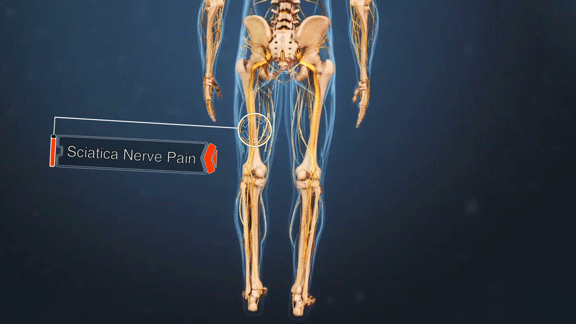

मानवी शरीरातील सर्वात लांब आणि महत्त्वाच्या मानल्या जाणाऱ्या नसांपैकी एक म्हणजे सायटिक नस (sciatic nerve). ही नस कंबरेपासून सुरू होऊन दोन्ही पायांच्या जवळपास घोट्यापर्यंत जाते. कुठल्याही कारणाने या नसेला इजा झाली तर कंबर, पाय, पार्श्वभाग अशा ठिकाणी असह्य वेदना होणं, क्वचित प्रसंगी पायातील शक्ती कमी झाल्यासारखं वाटणं, पायांना मुंग्या येणं, असा त्रास सुरू होतो. हा विकार म्हणजे सायटिका.

याची सुरुवात अचानक व तीव्र वेदनेने होते. ३० ते ५० वर्षांच्या लोकांमध्ये हा त्रास जास्त दिसतो आणि थंडीच्या दिवसांत हा त्रास वाढतो. विशेष म्हणजे सायटिकाच्या वेदना एकावेळी फक्त एकाच पायात होतात. बसताना, खोकताना किंवा शिंकताना जास्तच त्रास होतो. या वेदना जशा अचानक सुरू होतात तशाच अचानक नाहीशाही होतात.